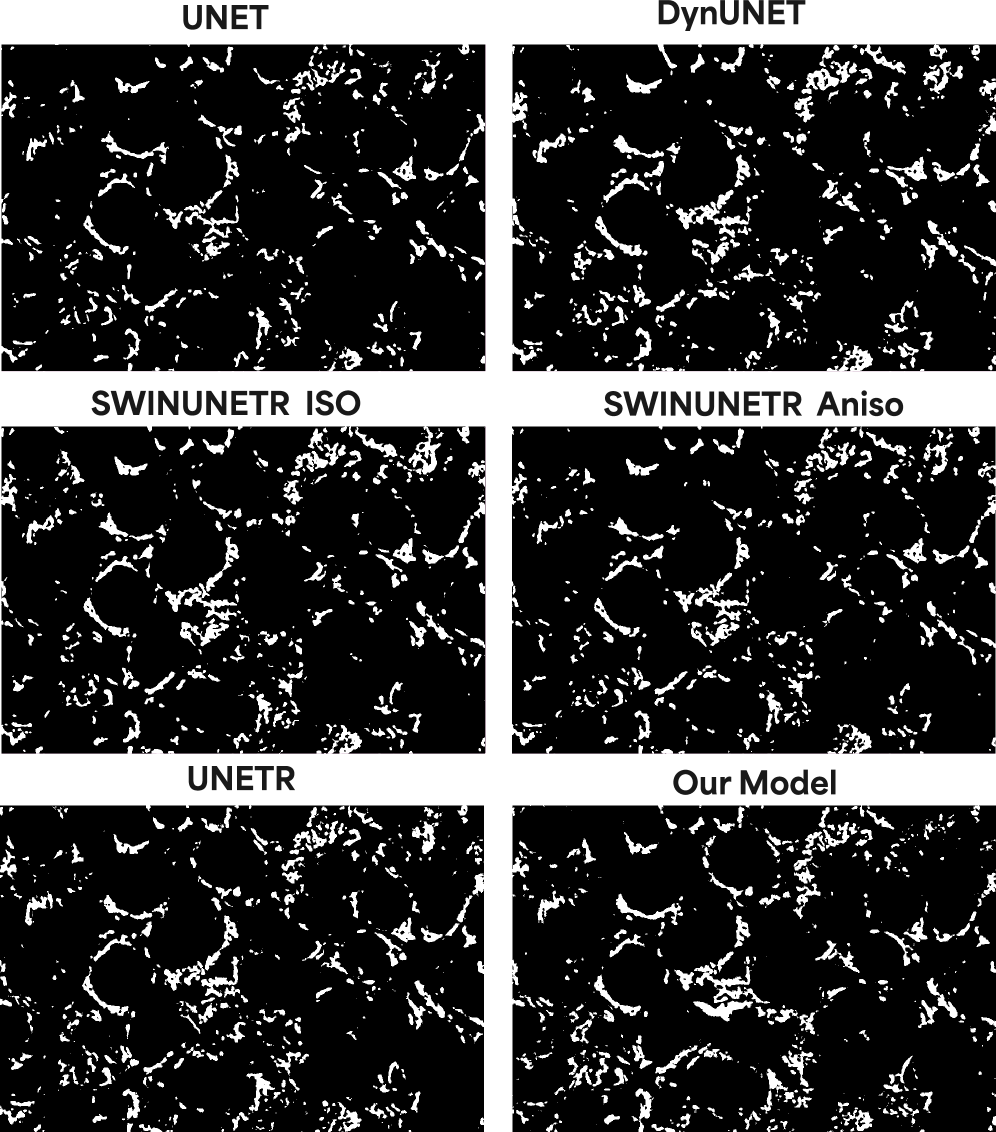

4.2 Mitochondria

We next evaluated our model on mitochondria, which we selected as an ideal intermediate validation target. This organelle poses a distinct challenge: its refractive index is significantly lower than that of nucleoli, resulting in a low-contrast signal, yet its tubular structures remain resolvable (i.e., above the diffraction limit).

Our model demonstrates high fidelity in this low-signal regime. It not only predicts the 3D location of the mitochondrial network—with high consistency at peripheral z-slices (top and bottom of the cell)—but also accurately resolves the orientation of individual tubules in sparse regions. This ability to capture fine-grained orientation from a convolved, low-contrast input strongly suggests the model is implicitly learning to invert the optical path and perform an effective deconvolution of the bright-field point spread function (PSF).

Architectural Benchmarks

We chose the number of parameters for each model based on empirical testing to make the comparison between our four billion parameter model as fair as possible. These parameter counts were the most effective for learning the mitochondria structure, and we found that anything below or above these either degraded the performance or added more compute with little to no gain in segmentation accuracy. More precisely, we noticed that for the base UNET, adding more parameters produced more blobby structures and focus shifted more on overall shape, while too few parameters learned the inherent brightfield noise. The transformer-based models produced reasonable results all within the range. One of our core innovations is seen in Table 1, wherein our model despite being four billion parameters only occupies an inference memory footprint of 26GB, which is several scales less than the dense networks. All models were tested with a batch size of one, and all image and patch sizes were the same across all models.

| Metric | UNet | DynUNet | UNETR | SwinUNETR | Ours (No MoE) | Ours |

|---|---|---|---|---|---|---|

| Params | 438M | 91M | 211M | 248M | 171M | 4B |

| IMF | 20GB | 51GB | 81GB | 110GB | 24GB | 26GB |

| Hausdorff | 57.94 | 57.94 | 50.98 | 53.41 | 56.55 | 46.08 |

| IoU | 0.396 | 0.319 | 0.368 | 0.362 | 0.287 | 0.42 |

| Precision | 0.496 | 0.369 | 0.452 | 0.452 | 0.341 | 0.532 |

| HD95 | 29.53 | 29.54 | 13.84 | 18.72 | 24.01 | 9.86 |

| Dice Score | 0.566 | 0.482 | 0.538 | 0.531 | 0.445 | 0.591 |

| Rel. Volume Error | 37.11 | 95.92 | 51.92 | 47.13 | 95.11 | 25.52 |

| Avg Surface Dist (mm) | 6.155 | 6.154 | 2.083 | 2.599 | 3.694 | 1.598 |

| Component Count Error | 694.61 | 677.06 | 1233.44 | 697.41 | 2898.16 | 1577.92 |